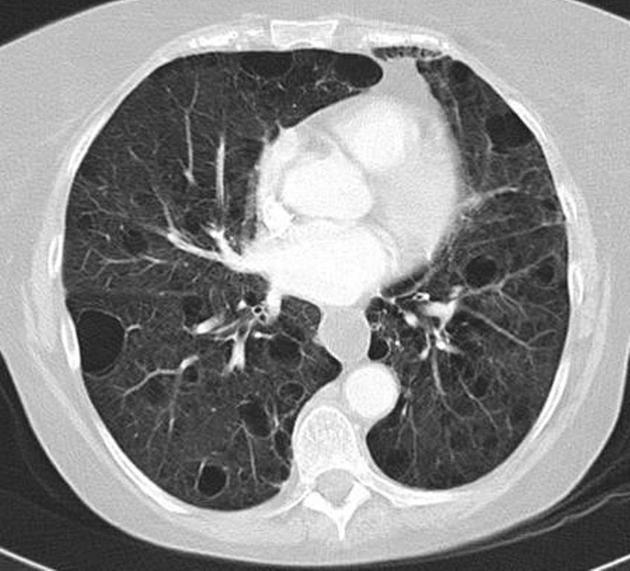

Diagnosis?

Other imaging findings?

Associations?

Proximal interruption of the (right) pulmonary artery. Can occur on either side, typically on the side opposite the aortic arch. The distal pulmonary vasculature receives blood from systemic collaterals.

Volume loss of the affected hemithorax and deviation of the mediastinum to the affected side.

Interruption of the left PA is associated with congenital heart disease, including tetralogy of Fallot and truncus arteriorus.